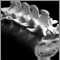

X-rays of the spine are usually normal. Further work-up may include a CT scan or MRI of the spine.